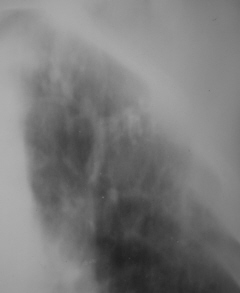

На фрагментах рентгенограмм (иллюстрации 3, 4), в прямой стандартной проекции слева под ключицей определяются полиморфные, различных размеров очаги.